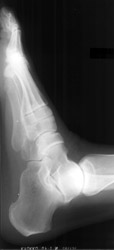

2. Erosion

pattern:

Erosions appear peripherally and progress to involve central area.

Erosions are described as having fuzzy margins. 'Pencil-in-cup' deformity

occurs when distal head of a bone becomes pointed appearing as if it had been

sharpened and the adjacent articulating surface becomes 'saucerized' through

erosions. Resorption of terminal tufts may also occur. In the feet, erosions

with fuzzy margins and bony proliferation may be observed along the posterior

and inferior aspect of the calcaneus at the attachment of Achilles tendon

and plantar aponeurosis. Bone proliferation may occur adjacent to erosions,

along shafts, across joints, and at tendinous or ligamentous insertion. Bone

proliferation along the shaft is observed as periostitis, usually described

as fluffy. Bone proliferation around distal phalanx of the great toe leads

to 'ivory phalanx" appearance. Bone production adjacent to erosions leads

to appearance of "mouse ears" .